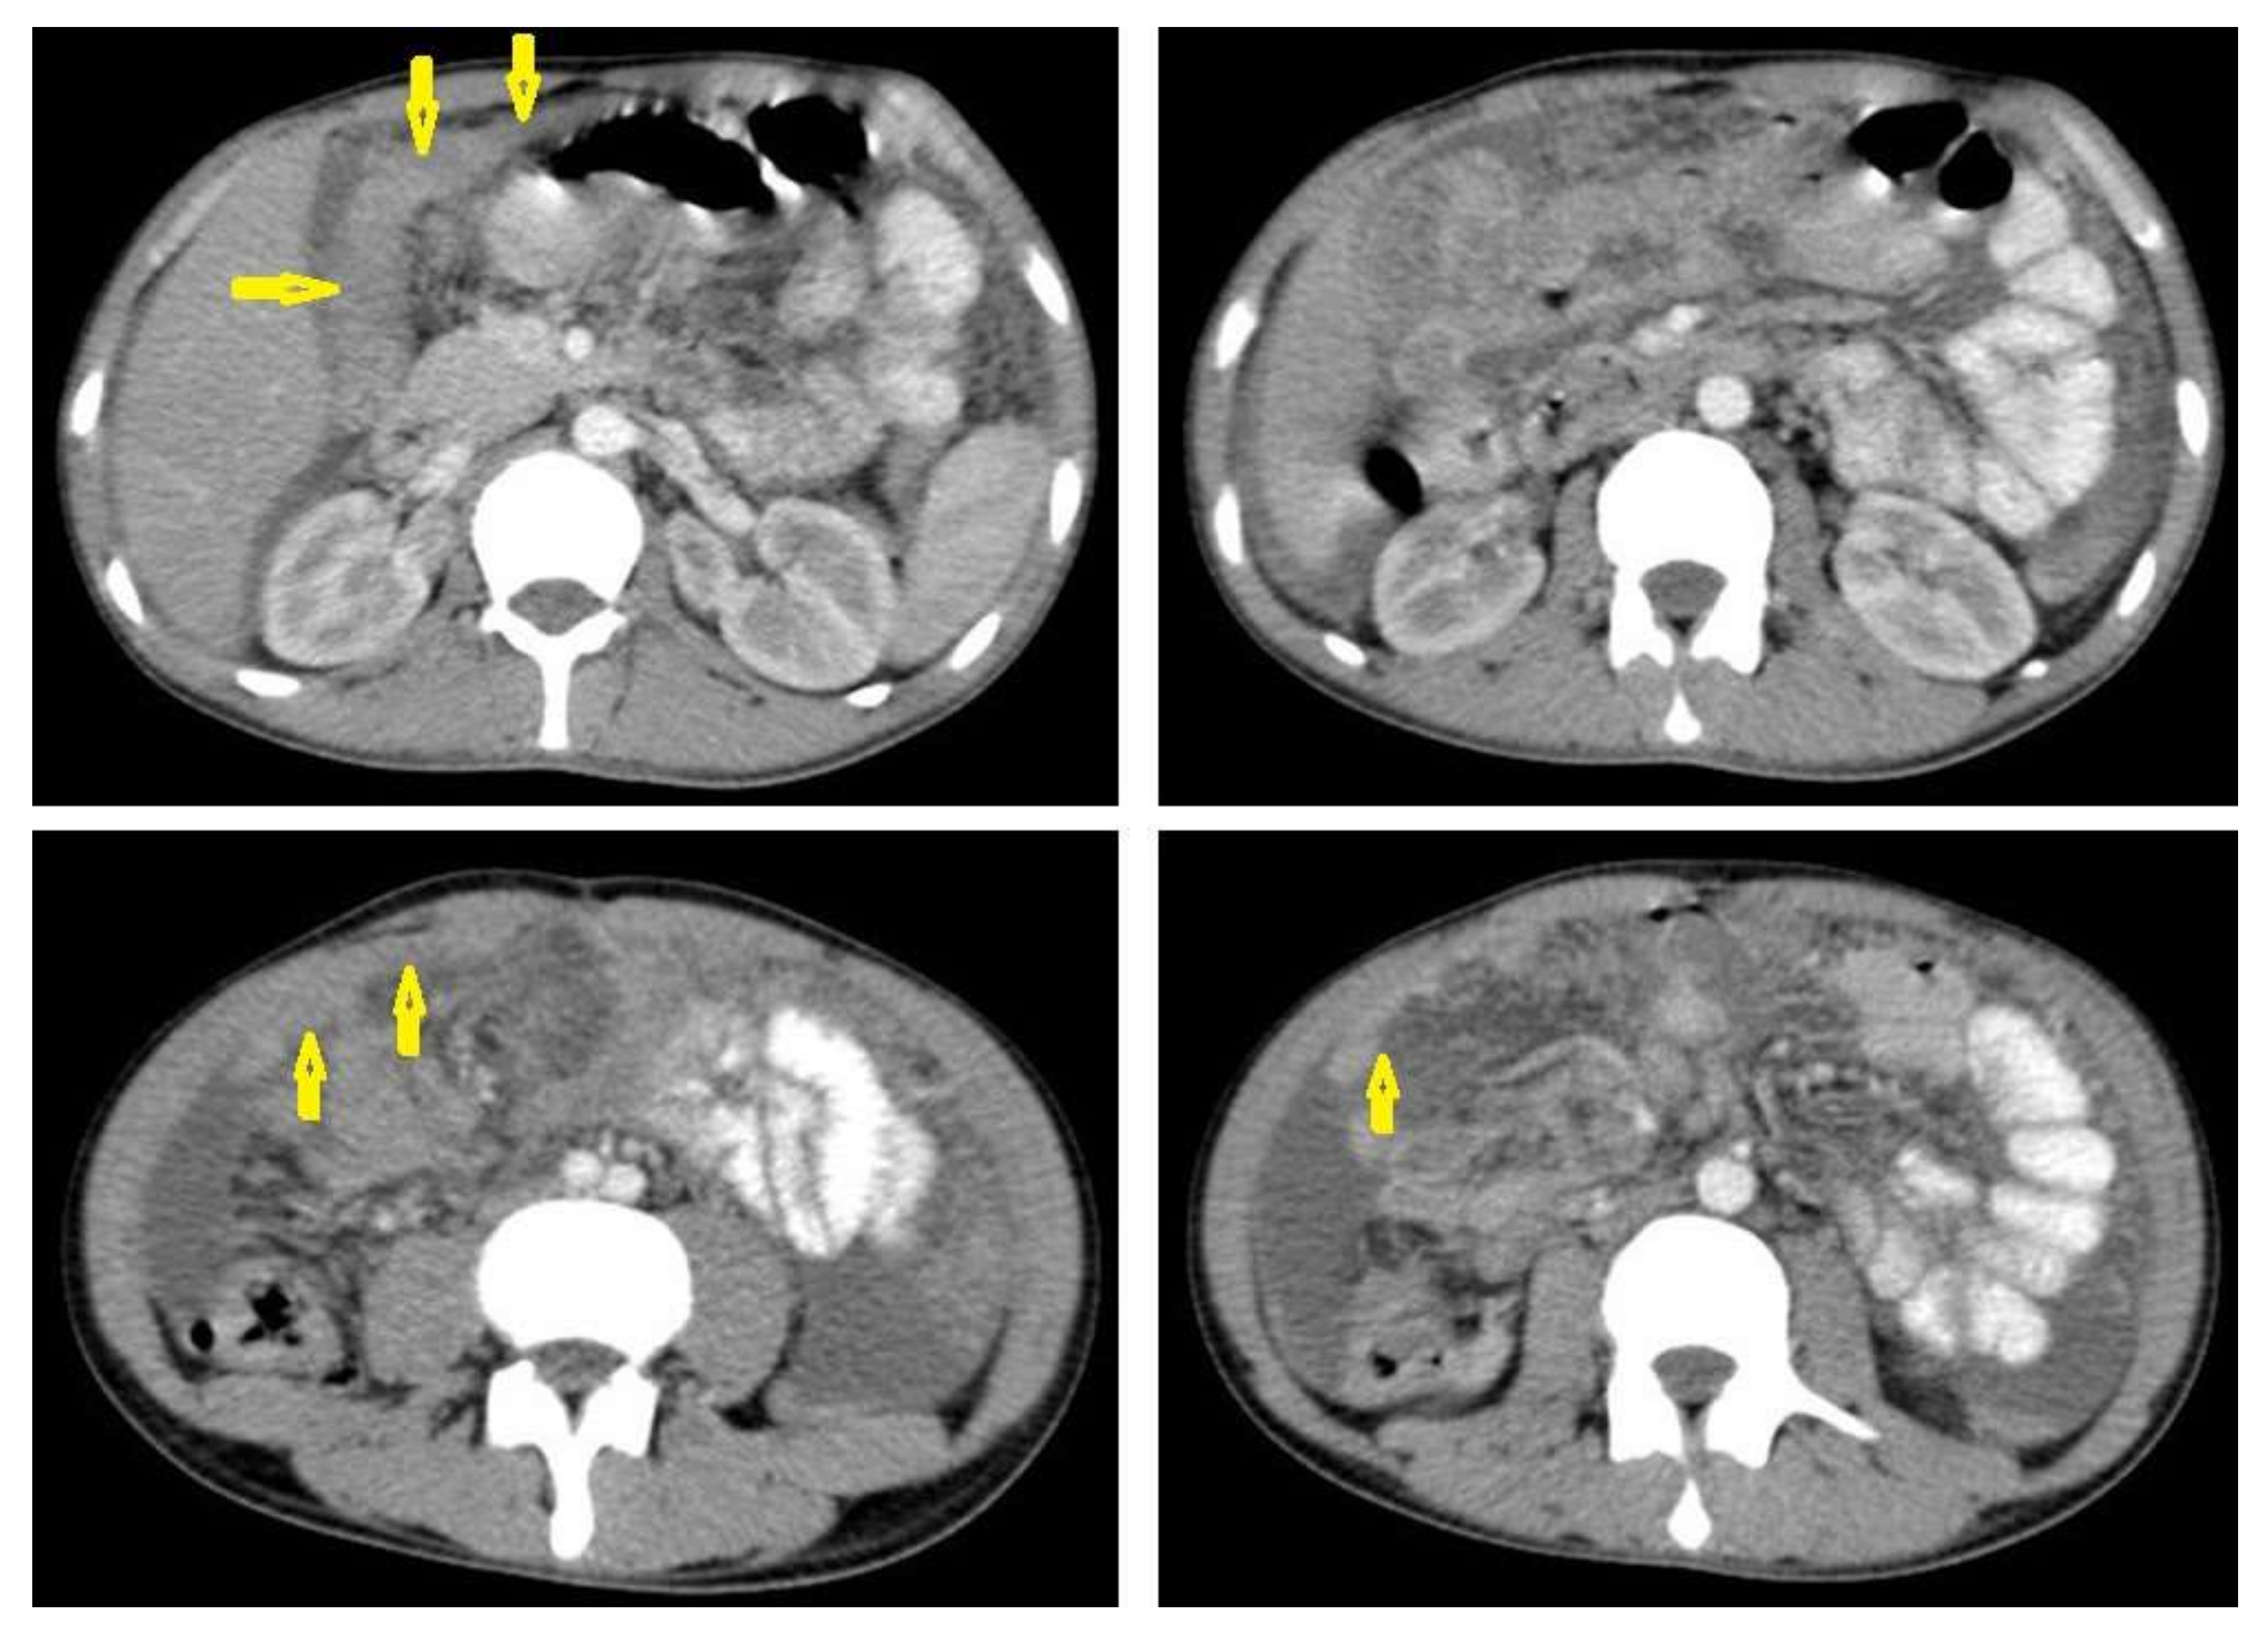

• Tuberculous lymphadenitis (Figure 20) is one of the most common radiological manifestation of abdominal TB which frequently involves multiple groups such as mesenteric and upper paraortic LNs. The majority of patients have enlarged lymph nodes with a low-attenuation center and peripheral-enhancing rim, which is characteristic of TB [45,46]. LNs may show peripheral rim enhancement, inhomogeneous, homogeneous, or no enhancement after contrast administration. Other patterns of LNs include conglomerate LNs with areas of necrosis, more than three enlarged or normal homogenous LNs in one section, or calcified LNs [45]. TB can mimic several other conditions, such as lymphoma, amebiasis, Crohn’s disease, and adenocarcinoma [47].

• Tuberculous peritonitis is the most common clinical presentation of abdominal TB. It involves the peritoneal cavity, mesentrium, and omentum. Peritonitis is believed to be originated from hematogenous spread or secondary to LN rupture, gastrointestinal dissemination, or fallopian-tube involvement [46,47]. Tuberculous peritonitis has three radiological patterns:

• Wet peritonitis (Figure 21) is the most common type that is characterized by free or loculated ascites with or without peritoneal thickening [46,47].

• Fibrotic peritonitis (Figure 22) is characterized by remarkable omental and mesenteric thickening forming cake-like masses with bowel loops enlargement and matting that can be seen by CT or ultrasound. [46,47].

• Dry peritonitis is characterized by mesenteric thickening with caseous nodules and fibrous adhesions [46,47].

Radiological features of tuberculous peritonitis can mimic nontuberculous infectious peritonitis, peritoneal carcinomatosis, peritoneal pseudomyxoma, and mesothelioma [46,47].

Figure 20. Tuberculous lymphadenitis in a 27-year-old women with cachexia, loss of appetite and cough. Axial abdominal CT image shows enlarged mesenteric, periaortic, and portahepatis lymph nodes (LNs), (short arrows) due to TB, which usually involves multiple groups, such as mesenteric and upper paraortic LNs. The image also shows relatively dense ascites and remarkable omental thickening forming cake-like mass (long arrow).

Figure 21. Wet peritonitis in a 16-year-old man with cachexia and loss of appetite. Selected axial abdominal images show marked relatively dense ascites and gross thickened omentum with faint enhancement of peritoneal reflections (long arrows) with multiple enlarged mesenteric and upper paraortic conglomerated lymph nodes (short arrows) with slight homogeneous enhancement.

Figure 22. Fibrotic peritonitis in a 20-year-old man with fatigue, abdominal distension, and loss of appetite. Selected axial images of abdominal CT show remarkable omental thickening, forming cake-like masses (arrows) with faint enhancement and mild smooth thickening of peritoneal reflections associated with mild-to-moderate dense ascites and several low-attenuation mesenteric lymph nodes that are challenging to be distinguished from small bowel loops.